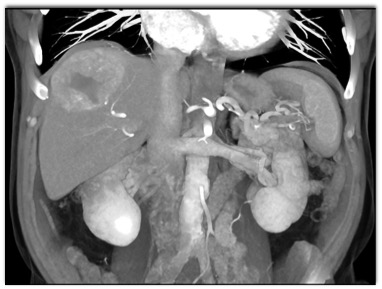

The best diagnosis for this hepatic mass is?

hepatoma

cholangiocarcinoma

hemangioma

FNH